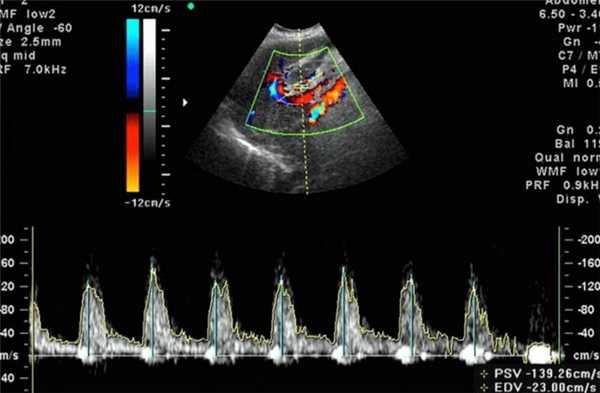

Но лидером в исследованиях гемодинамических процессов в сердце и сосудах плода считается доплер-эхокардиография.Этот метод оценивает три основных показателя -направление, скорость и характер кровотока. Процедура такова:на животе беременной устанавливается датчик УЗИ. На экран передается цветное изображение. Красным обозначается течение крови, которая двигается в сторону датчика.Синий цвет указывает на объем крови, идущий в обратном направлении. Максимальная интенсивность того или иного цвета обозначает повышенную гемодинамику.

Допплеркардиография, позволяющая оценить кровоток, информативна лишь при выраженном сужении аорты [18]. При этом возникает обратная зависимость максимальной скорости кровотока в восходящем и нисходящем отделах аорты. В норме скорость в восходящем отделе немного преобладает над скоростью нисходящего отдела.

Важное дополнительное значение имеет допплерэхокардиографическое исследование, которое при коарктации орты позволяет выявить ускорение и турбулентный характер кровотока в аорте. Однако в антенатальном периоде этот признак может не проявиться [2]. Более надежно выявление левоправого шунта через овальное окно. Предполагается, что этот шунт является компенсаторным механизмом, обеспечивающим уменьшение потока крови в левый желудочек и аорту. G. Sharland и соавт. [18] отметили левоправый шунт через овальное окно у 7 из 12 плодов с коарктацией аорты. У оставшихся 5 плодов обнаруживалось как левоправое, так и праволевое направления потоков крови через овальное окно.